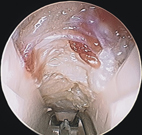

然而在微創內視鏡輔助術式,在手腕處切開一公分的橫向傷口,手術時間較短且對組織破壞少,術後復原較快。(如圖一)

圖一、微創內視鏡輔助術式示意圖